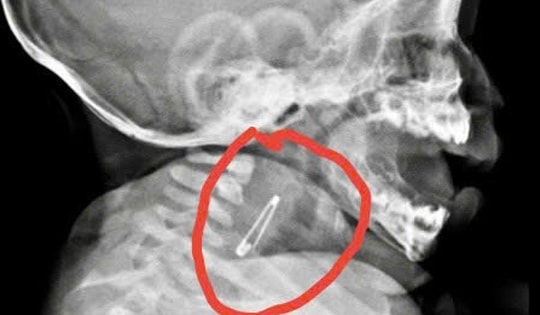

Bé 5 tháng tuổi vào viện cấp cứu khẩn vì nuốt kim băng đã bung mở